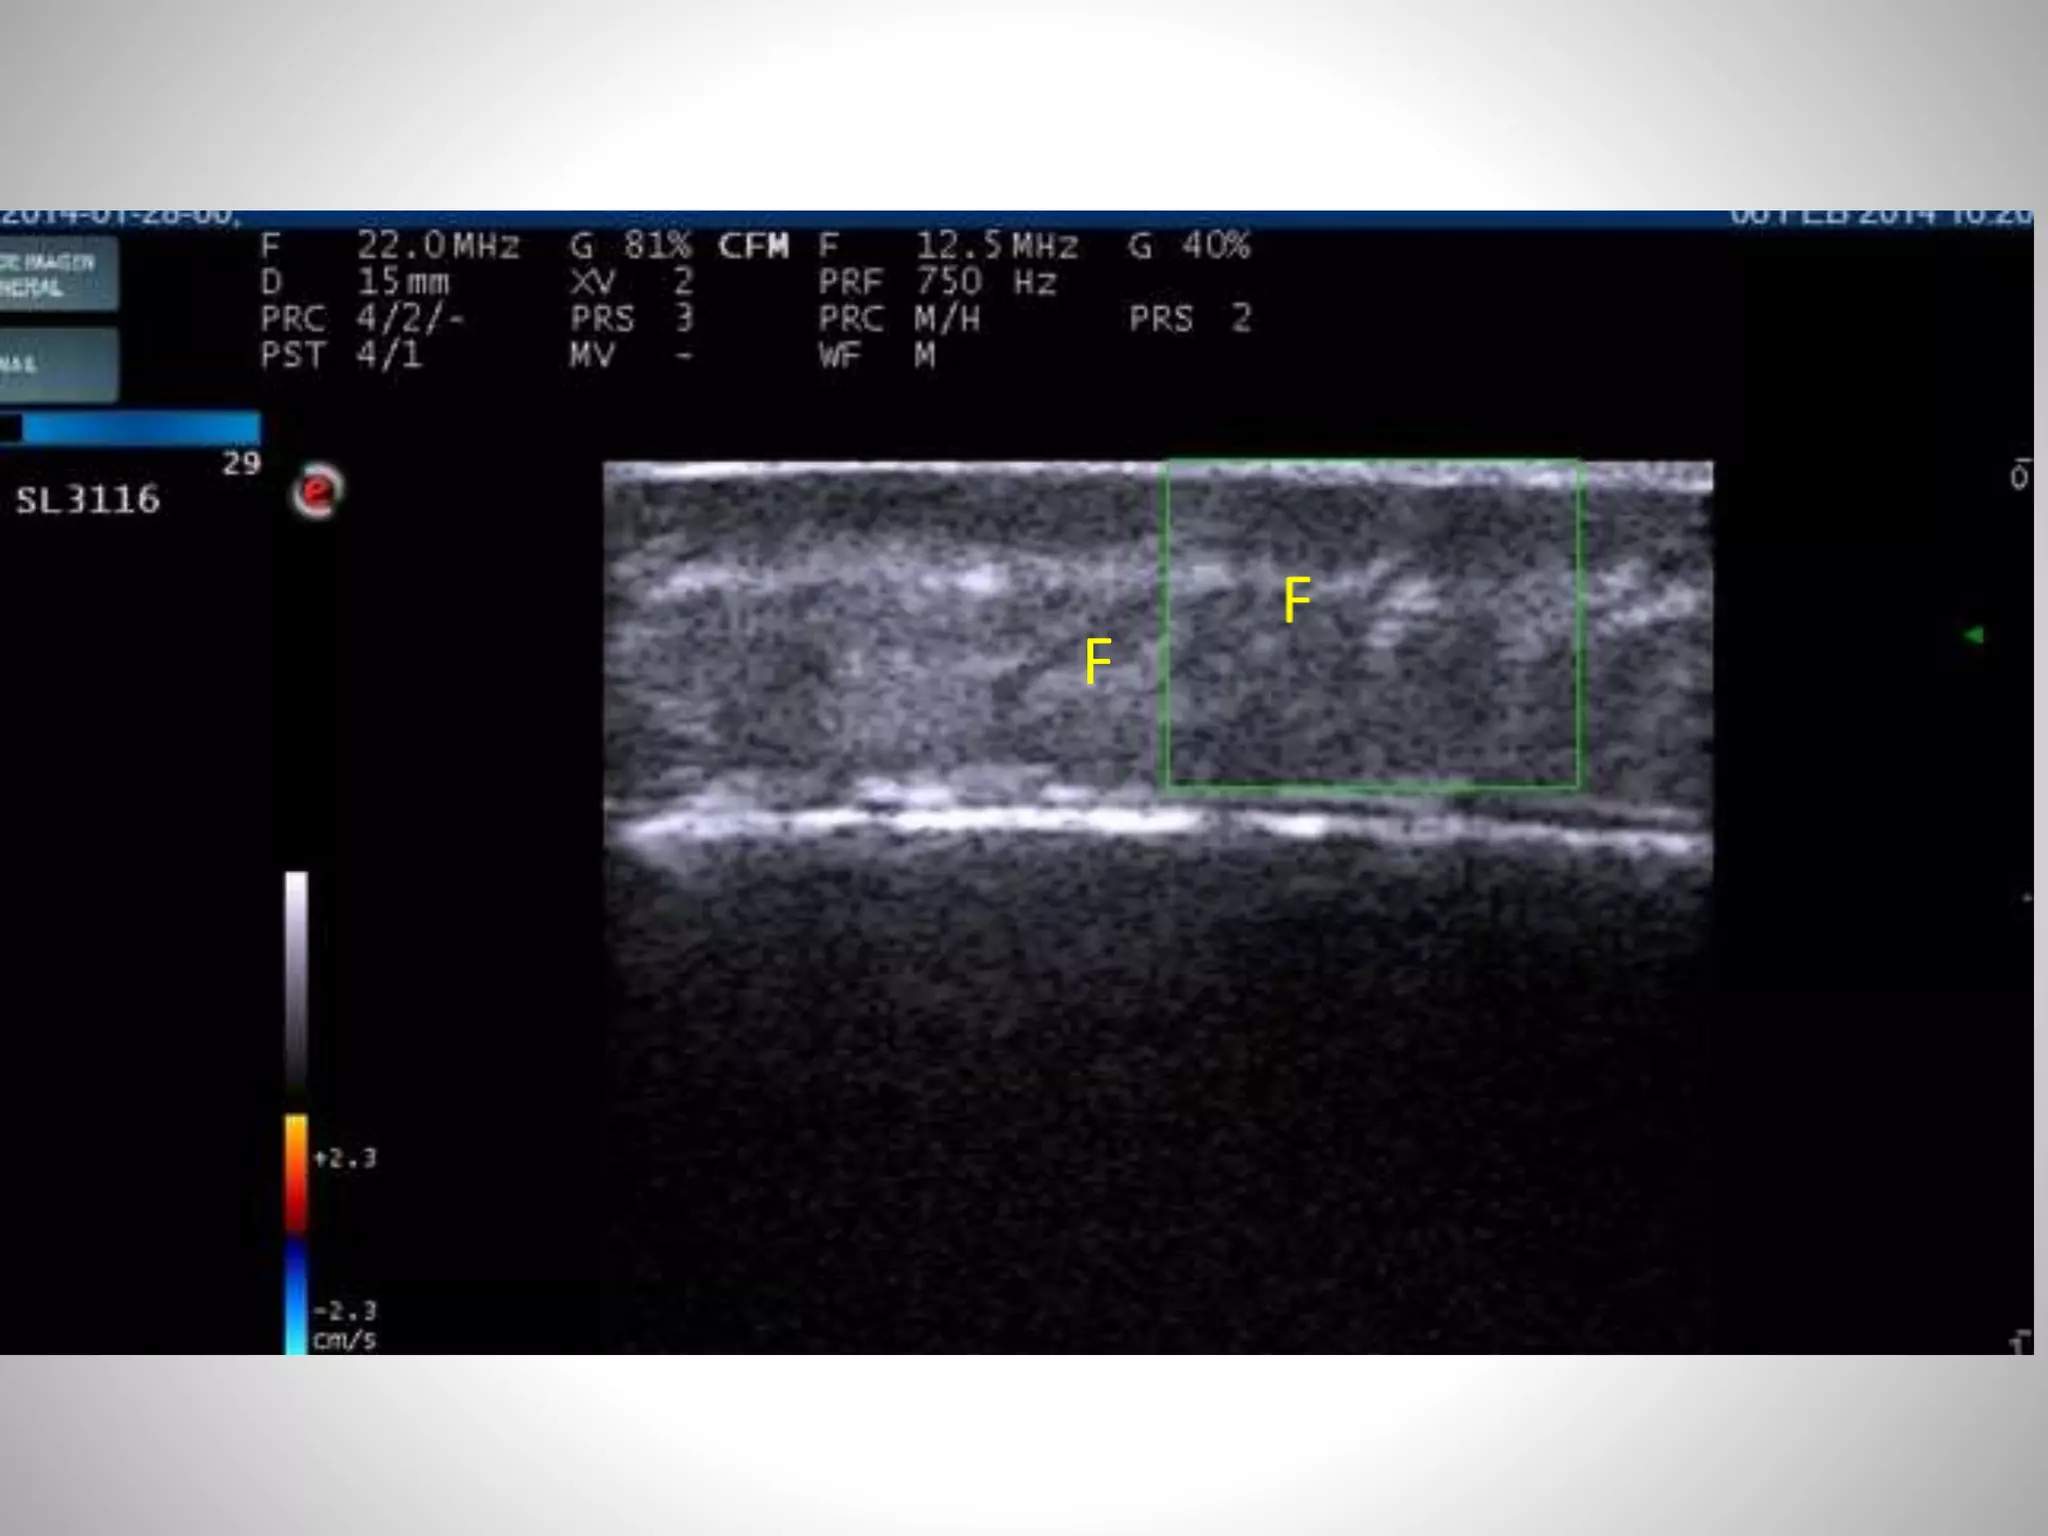

FOLICULO PILOSEBACEO

FOLÍCULO PILOSEBACEO

Alfageme F, Cerezo E. Ecografía de las enfermedades foliculares , Actualidad medica 2014,

(in press)

F